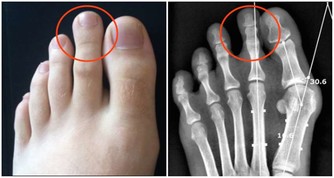

先來看看你的牙齦是不是已經是這樣了:

所以洗牙會出血那是因為你的牙齦已經發炎了!當結石碎裂脫離牙面時,

碰到有炎症的牙齦就會引起出血,所以洗牙時出血多少也是反應炎症嚴重程度的一個指標。